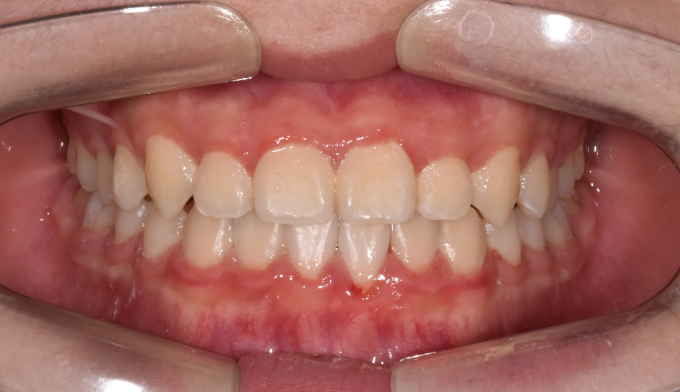

주걱턱, 그리고 앞니가 거꾸로 물리는 ‘반대교합’은 비슷한 말이 아닙니다. 서로 전혀 다른 원인과 치료 방법을 가지고 있습니다.

주걱턱은 턱 자체의 길이가 긴 경우이고, 반대교합은 위아래 앞니 사이의 관계를 지칭하는 말입니다.

턱뼈의 성장이 정상인 경우에는 턱교정 필요없이 앞니만 제대로 넘겨주면 훨씬 간단하고 효율적인 교정치료가 가능합니다.

본 케이스의 홙자는 턱뼈의 모든 수치가 정상이었으므로 치아만 적절히 교정하여 안모의 개선까지 만들어낸 경우입니다. 교정기간은 11개월 소요되었습니다.